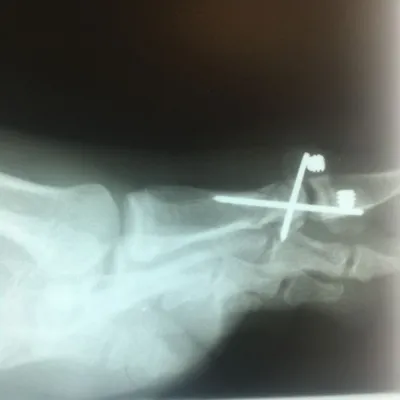

Pre and Postop ORIF Displaced Big Toe Intra-articular Pediatric Fracture (Below)

Below is an x-ray image of an extra-articular fracture of the proximal phalanx of the hallux (great toe) of a child. the fracture line does not enter the joint.

First Metatarsal Fracture